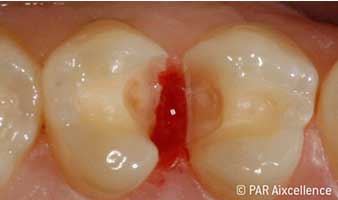

Рис. 3. При первоначальном раскрытии кариозной полости четко видны пораженные ткани

Рис. 4. Изображение, как на рис. 3, на этот раз с использованием Facelight